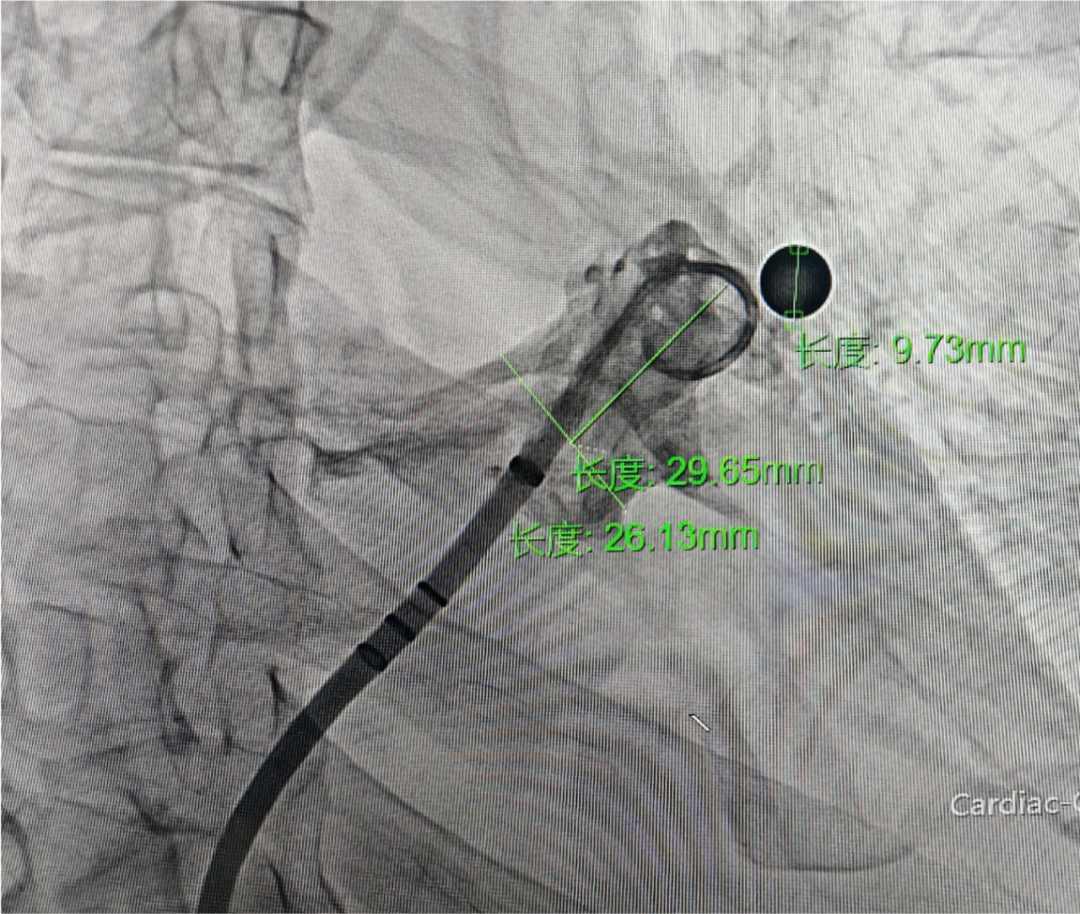

DSA下肝位造影+测量

肝位测量,开口26.13 mm,深度29.65 mm

封堵策略:术前CT报告为“风向袋型”左心耳。术中DSA肝位造影测量开口26.13mm,可用深度29.65mm;DSA右肩位造影测量开口22.67mm,深度21.51mm,心耳为“鸡翅型”左心耳,深度空间充分,综合考虑选择MemoLefort LAFDQ-29封堵器,退鞘法展开封堵器,保证封堵器稳定释放。

术中DSA肝位造影测量开口26.13mm,可用深度29.65mm;DSA右肩位造影测量开口22.67mm,深度21.51mm,心耳为“鸡翅型”左心耳,深度空间充分,综合考虑选择MemoLefort LAFDQ-29封堵器;MemoLefort封堵器远端为花苞型内扣保护,顺应性强,阻流膜高度覆盖,能更好适应心耳(包括浅心耳)内部结构及形态,达到稳定锚定。